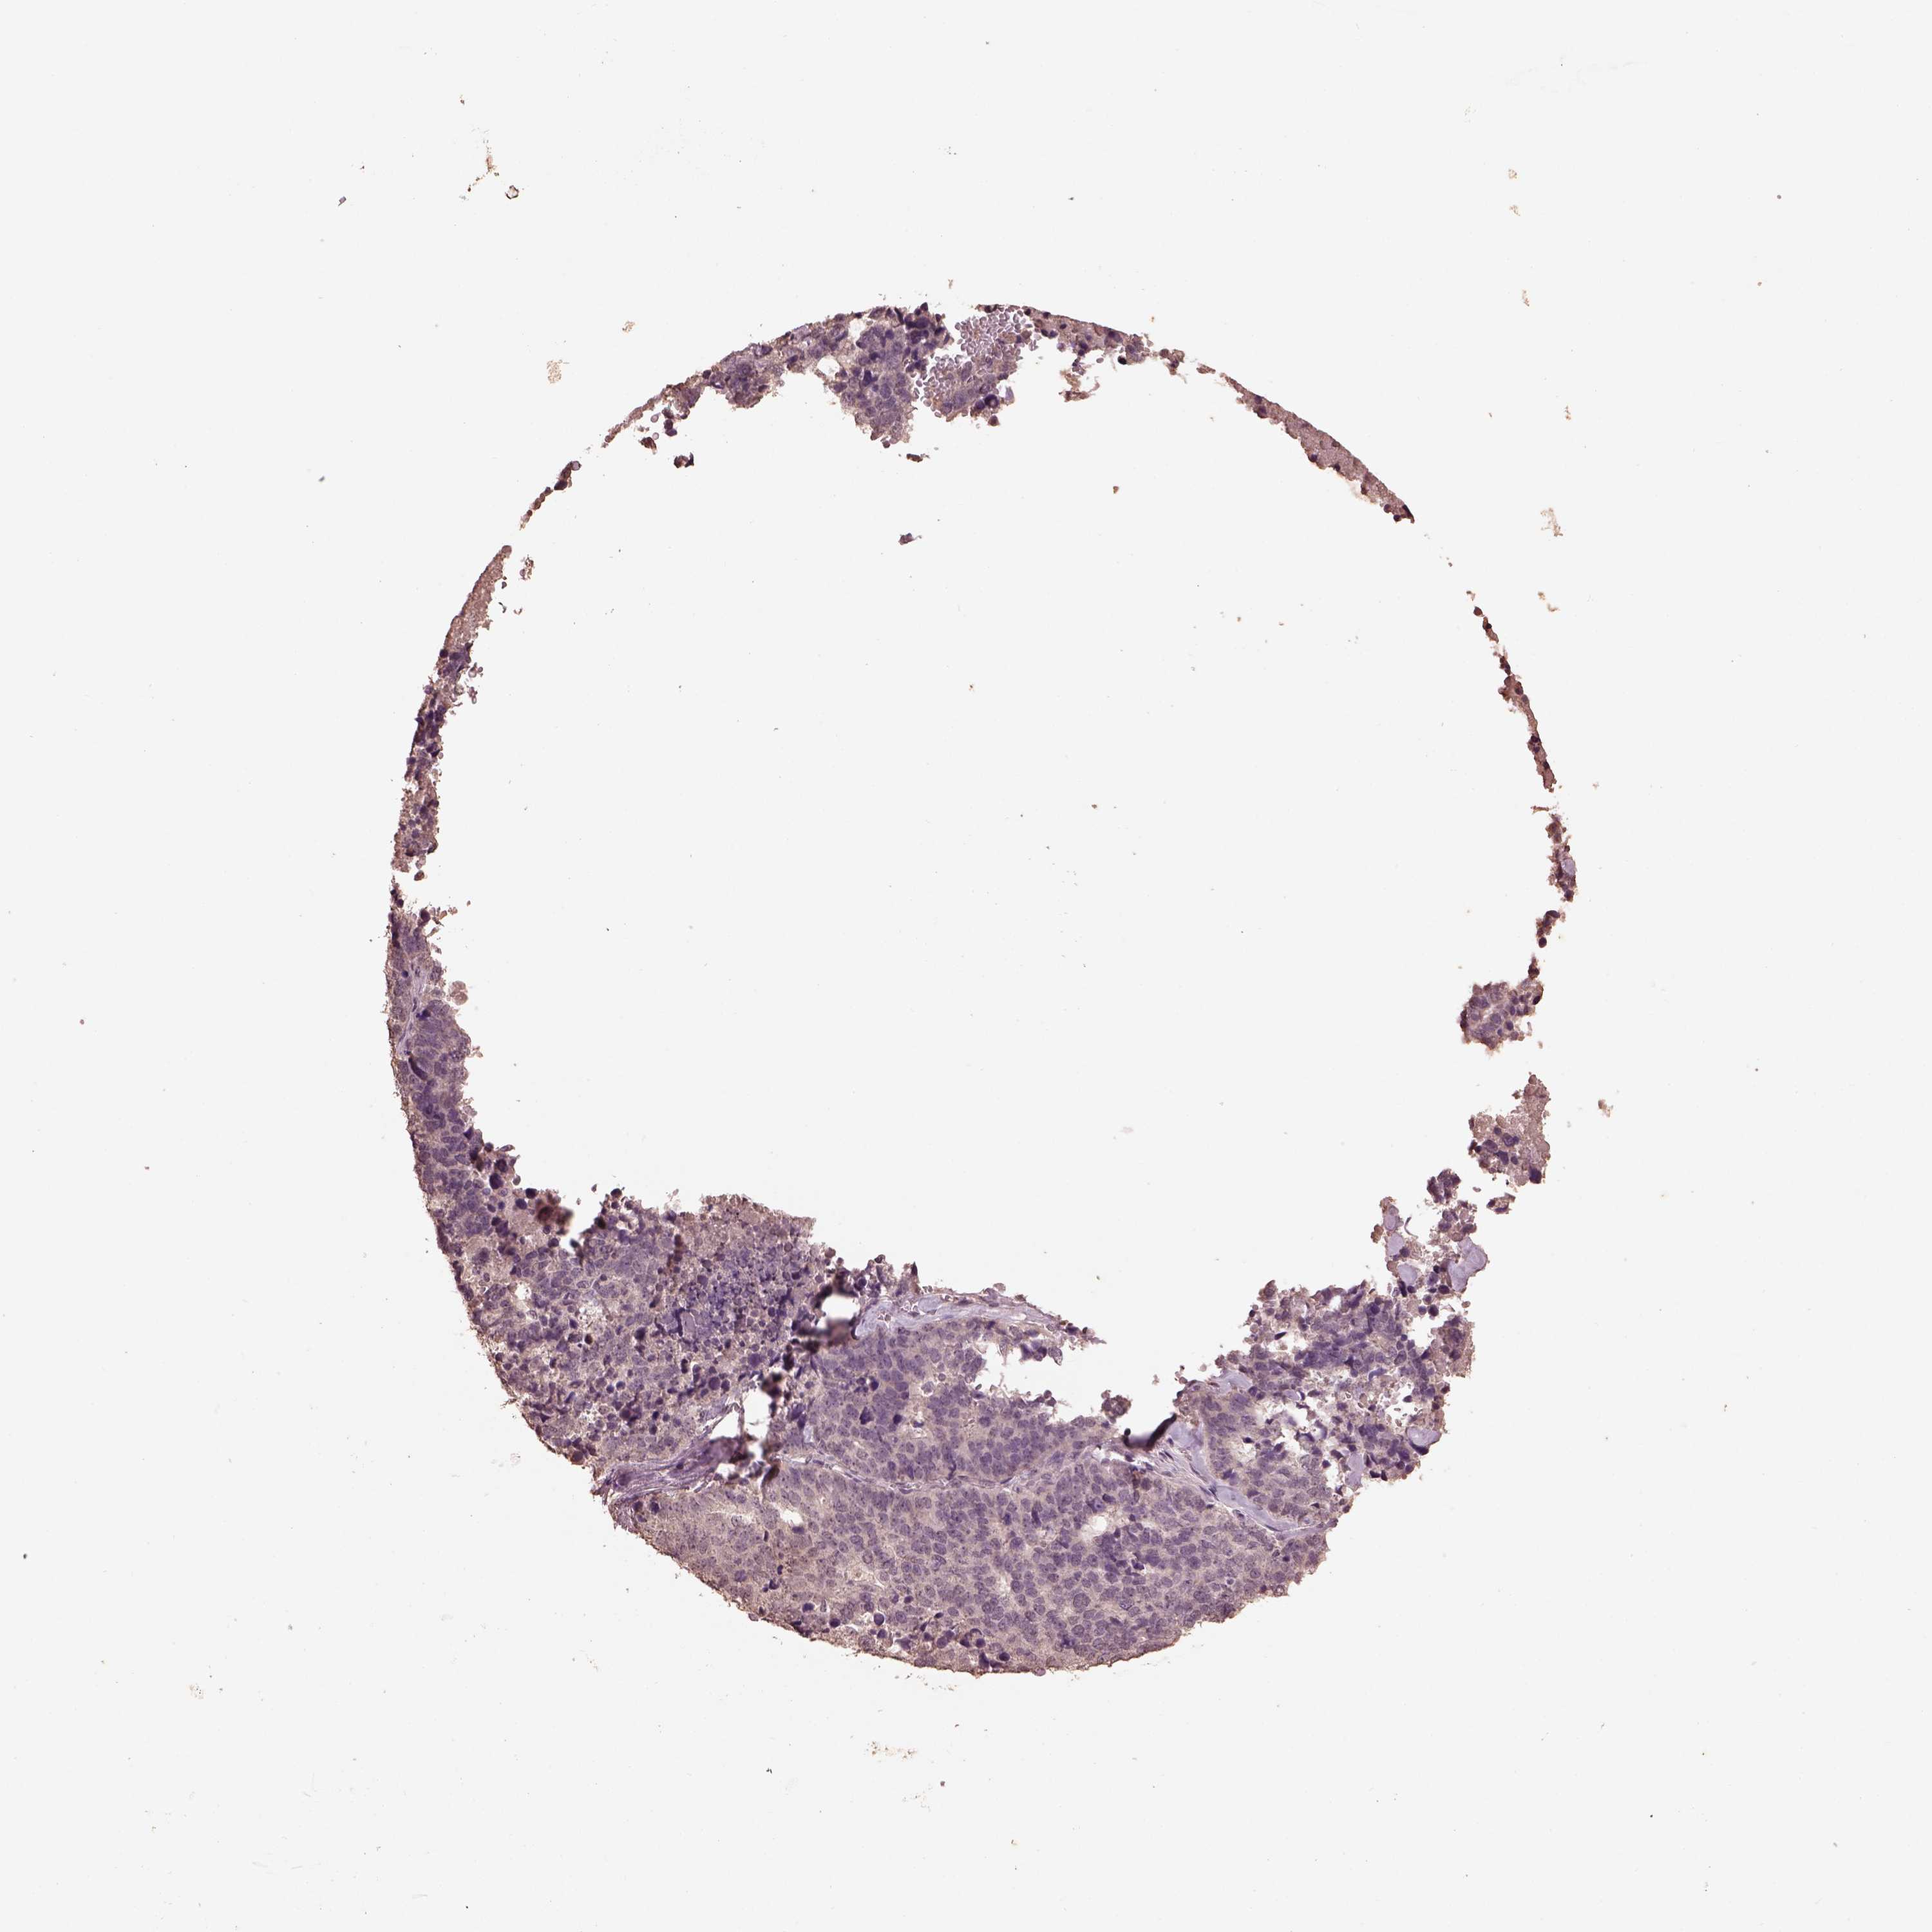

STOMACH CANCER - Protein expressioni

A mouse-over function shows sample information and annotation data. Click on an image to view it in a full screen mode. Samples can be filtered based on level of antibody staining by selecting one or several of the following categories: high, medium, low and not detected. The assay and annotation is described here.

Antibody stainingi

Antibody staining in the annotated cell types in the current human tissue is reported as not detected, low, medium, or high, based on conventional immunohistochemistry profiling in selected tissues. This score is based on the combination of the staining intensity and fraction of stained cells.

Each image is clickable and will lead to virtual microscopy that enables deeper exploration of all samples and also displays staining intensity scores, fraction scores and subcellular localization as well as patient and tissue information for each sample.

Antibody HPA063621

Staining

High

Medium

Low

Not detected

Intensity

Strong

Moderate

Weak

Negative

Quantity

>75%

75%-25%

<25%

None

Location

Nuclear

Cytoplasmic/membranous

Cytoplasmic/membranous,nuclear

Adenocarcinoma, NOS